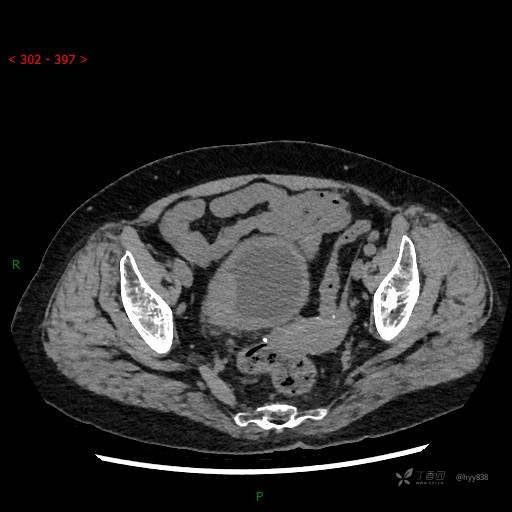

辅助检查:CT

膀胱CT平扫(2022.10.20)

增强(2022.11.1)